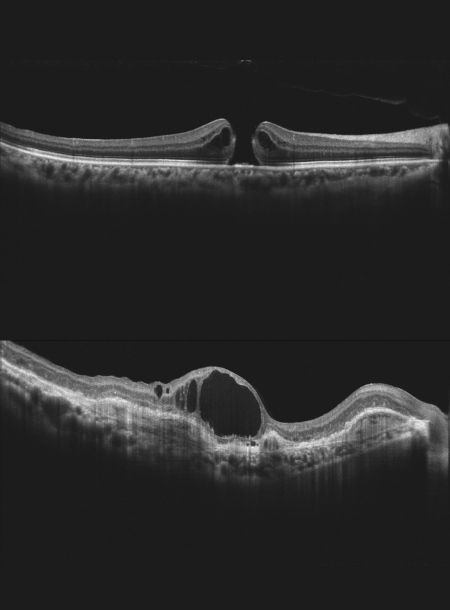

• Висока якість ОКТ-зображення

• Глибина сканування 3 мм показує деталізоване зображення склоподібного тіла, сітківки та судинної оболонки

Режим глибокої судинної томографії (DCI)

Використання глибокої судинної томографії для виявлення неоваскуляризації судинної оболонки.

Система Mocean® 3000 пропонує 8 моделей сканування, які допоможуть вам підвищити ефективність діагностики:

Сітківка (HD лінійне та шестилінійне сканування, мульти, 3D куб),

Глаукома (Диск глаукоми для аналізу ONH, сканування макулярної області для аналізу GCC),